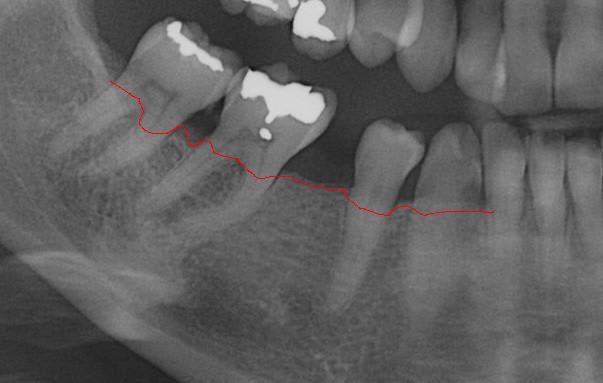

25/09/2013 à 22h19

Empreinte, détourage et préparation des cires avec une occlusion différente de celle du wax up, un peu plus de DV

Le trait rouge sur les incisive donne à peu de chose prêt l'origine...